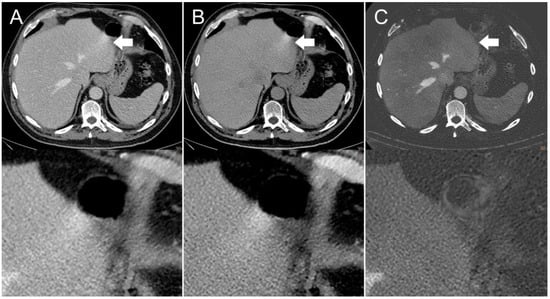

Figure 2. Axial contrast-enhanced CT scan of a 65-year-old man. Streak artifact (indicated by arrows) on the left liver lobe originating from peristaltic motion of the stomach visible in the (A) conventional 120 kVp image and (B) virtual non-contrast (VNC) image reconstruction. The streak artifact is markedly reduced in the (C) iodine image reconstruction, resulting in a better visibility of the underlying liver tissue.

The presence of visible intestinal peristalsis-related streak artifacts on the liver was significantly lower (p < 0.001) in the iodine image reconstructions with 18/208 (9%) compared with the conventional 120 kVp images with 51/208 (25%) (see Figure 2, Figure 3 and Figure 4). The presence of visible peristalsis-related streak artifacts on the liver was not significantly lower in 40 keV monoenergetic image reconstructions with 48/208 (23%) (p = 0.15), 200 keV monoenergetic image reconstructions with 51/208 (25%) (p = 1.0), or VNC image reconstructions with 50/208 (24%) (p = 1.00) compared with conventional 120 kVp images.